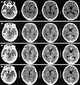

Severe intellectual deficit

Borderline intellectual functioning, also called borderline mental retardation (in the ICD-8), is a categorization of intelligence wherein a person has below average cognitive ability (generally an IQ of 70–85), but the deficit is not as severe as intellectual disability (below 70). It is sometimes called below average IQ (BAIQ). [Source: Wikipedia ]